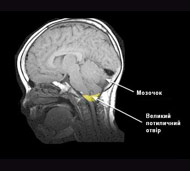

Синдром Арнольда-Кіарі - це аномалія розвитку головного мозку, при якій відділ черепа, що містить мозочок, є занадто малим або деформованим, внаслідок чого відбувається здавлювання мозку. Найнижча частина мозочка або мигдалики зміщені у верхню частину каналу хребта. Педіатрична форма - синдром Арнольда-Кіарі III типу - завжди асоціюється з мієломенінгоцеле (кила спинного мозку та мозкових оболонок). Доросла форма - синдром Кіарі I типу - розвивається через недостатньо велику задню частину черепа.

Коли мозочок вдавлюється у верхню частину каналу хребта, він може перешкоджати нормальному відтоку ліквору, який захищає головний і спинний мозок. Порушена циркуляція ліквору може призвести до блокади сигналів, які передаються від головного мозку до нижче лежачих органів або до скупчення спинномозкової рідини в головному і спинному мозку. Тиск мозочка на спинний мозок або нижню частину стовбура мозку може викликати сірінгомієлію.

Якщо ви страждаєте від головного болю, але причина цього симптому не ясна для лікаря, вас попросять пройти магнітно-резонансну томографію (МРТ), яка допоможе виявити, чи є у вас аномалія Кіарі.

Іноді перед обстеженням необхідно ввести контрастну речовину, за допомогою якої, при її попаданні в мозок, підвищується контрастність і чіткість зображення. МРТ - це безпечний і безболісний тест. У подальшому за допомогою повторної МРТ можна буде вести моніторинг прогресування цього захворювання.